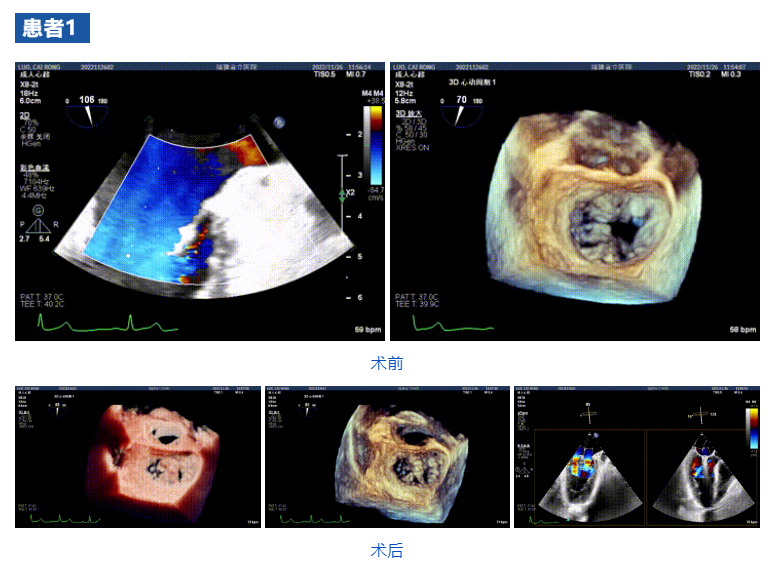

接受治療的三例患者均為器質(zhì)性重度二尖瓣反流(DMR)患者,術(shù)前超聲提示二尖瓣后葉脫垂伴4+反流,左室舒張功能減退。郭延松教授攜同團(tuán)隊成員陳新敬副教授和洪景宣、方明程、楊清勇主治醫(yī)師、心外科丁杭主任以及超聲科賴寶春、葉振盛主治醫(yī)師共同進(jìn)行病情討論。考慮到患者高齡、基礎(chǔ)疾病多、STS評分高,為外科手術(shù)極高危患者,不適合進(jìn)行外科開胸二尖瓣手術(shù),因此決定為患者實施經(jīng)導(dǎo)管緣對緣修復(fù)介入術(shù)(JensClip經(jīng)導(dǎo)管瓣膜夾系統(tǒng))。

在浙江大學(xué)醫(yī)學(xué)院附屬第二醫(yī)院王建安教授團(tuán)隊的支持下,手術(shù)經(jīng)股靜脈-房間隔入路,采用全身麻醉插管,在TEE和DSA引導(dǎo)下完成房間隔穿刺。置入JensClip瓣膜夾系統(tǒng)后,在左房調(diào)整瓣膜夾的位置和軸向,后進(jìn)入左室,在TEE引導(dǎo)下捕捉二尖瓣前后瓣葉,并關(guān)閉瓣膜夾。經(jīng)TEE反復(fù)確認(rèn)手術(shù)效果后最終鎖定并釋放瓣膜夾。術(shù)后即刻超聲顯示瓣膜夾位置穩(wěn)定,功能良好,二尖瓣反流由術(shù)前4+減少至微量,手術(shù)圓滿成功。